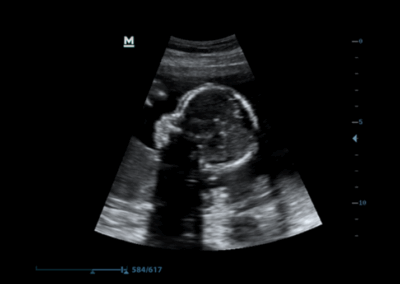

Z60

Sistema de diagnóstico ecográfico.

El sistema Z60 es una buena opción para aquellos que requieren un rendimiento de imagen de alta calidad, una movilidad simple y asequibilidad cuando se trata de imágenes ecográficas avanzadas. Con configuraciones completas y un diseño integrado, el Z60 es el resultado de los esfuerzos continuos y decididos de Mindray para hacer que la atención médica primaria sea más eficiente, eficaz y accesible para todos.